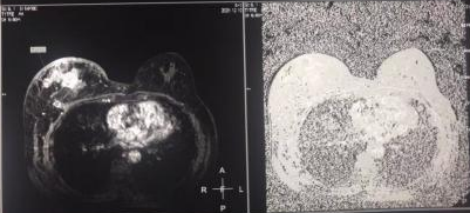

2021年12月8日,双侧乳腺钼靶影像表现:右乳外上可见高密度肿物影,大小约6.7×6.2cm,形态不规则,密度不均匀,边缘可见分叶,另可见粗大钙化,皮肤增厚,乳头未见异常;左乳末见异常。右腋下可见增大淋巴结,最大者短径约1.7cm,左侧腋下可见小淋巴结。印象:右乳恶性肿瘤伴腋下淋巴结转移,BI-RADS分级为5级。

图1.右乳及右腋下钼靶